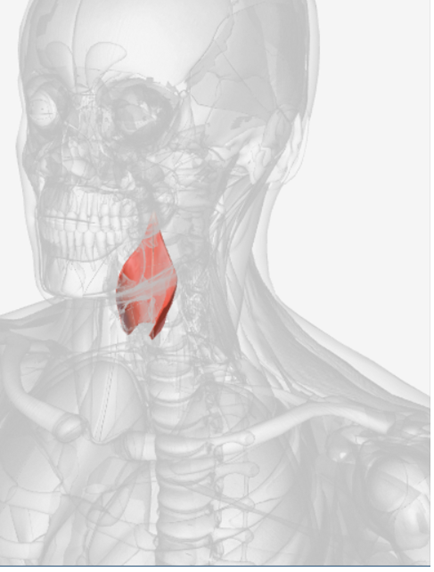

Masseter

origin is the zygomatic arch, coursing down to insert into the ramus of the mandible and the coronoid process, function is the elevate the mandible

Temporalis

origin is the temporal and parietal bones of the cranium, coursing down and forward through the zygomatic arch, to insert on the coronoid process and the ramus of the mandible; function is to elevate the mandible and draw it back if protruded